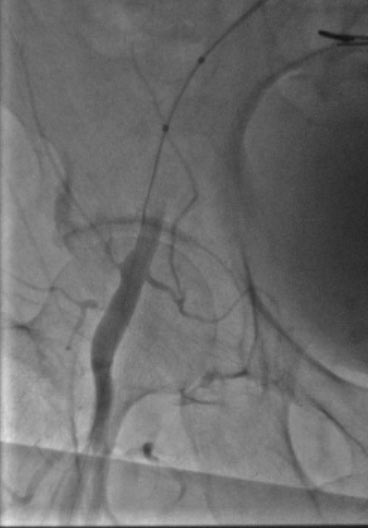

#protectedpci #RadialFirst #impella #safefemoral#ivus##unprotectedleftmainpci 61f#nstemi.6f45pinnacle inside 14f sheath .Successful #LMpci .left cfa occluded. bailout 014”grand slam/8x2balloon via rt radial. failed preclose ,safe balloon hemostasis while act240sec.#NoHematoma

istentem's tweet image. #protectedpci #RadialFirst #impella #safefemoral#ivus##unprotectedleftmainpci 61f#nstemi.6f45pinnacle inside 14f sheath .Successful #LMpci .left cfa occluded. bailout 014”grand slam/8x2balloon via rt radial. failed preclose ,safe balloon hemostasis while act240sec.#NoHematoma